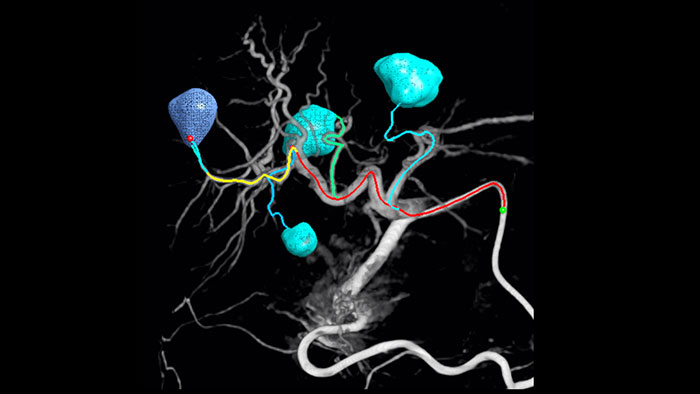

A adoção de técnicas de quimioterapia/radioembolização, tais como TACE e SIRT, impulsiona a necessidade de padronização e eficiência. Caso após caso, o utilizador deve localizar os tumores de forma fiável e consistente, identificar todos os vasos do alimentador e planear/executar a abordagem de intervenção adequada. A nossa solução de deteção automática do alimentador pode melhorar significativamente a deteção da artéria de alimentação em comparação com a utilização independente do TC do feixe cónico. O EmboGuide ajuda a maximizar a eficácia dos procedimentos TACE, uma vez que melhora potencialmente a sua sensibilidade, reduz falsos positivos e maximiza a concordância entre leitores.1

A capacidade de detetar e diferenciar nódulos hepáticos e identificar pequenos vasos de alimentação é fundamental para determinar a terapia adequada. Navegar para a região de interesse alcançando todos os alimentadores, enquanto permanece seletivo para a lesão, aumenta a oportunidade de sucesso. A confirmação do ponto final do tratamento e do sucesso do tratamento enquanto o paciente ainda está na mesa aumenta a confiança do resultado clínico.